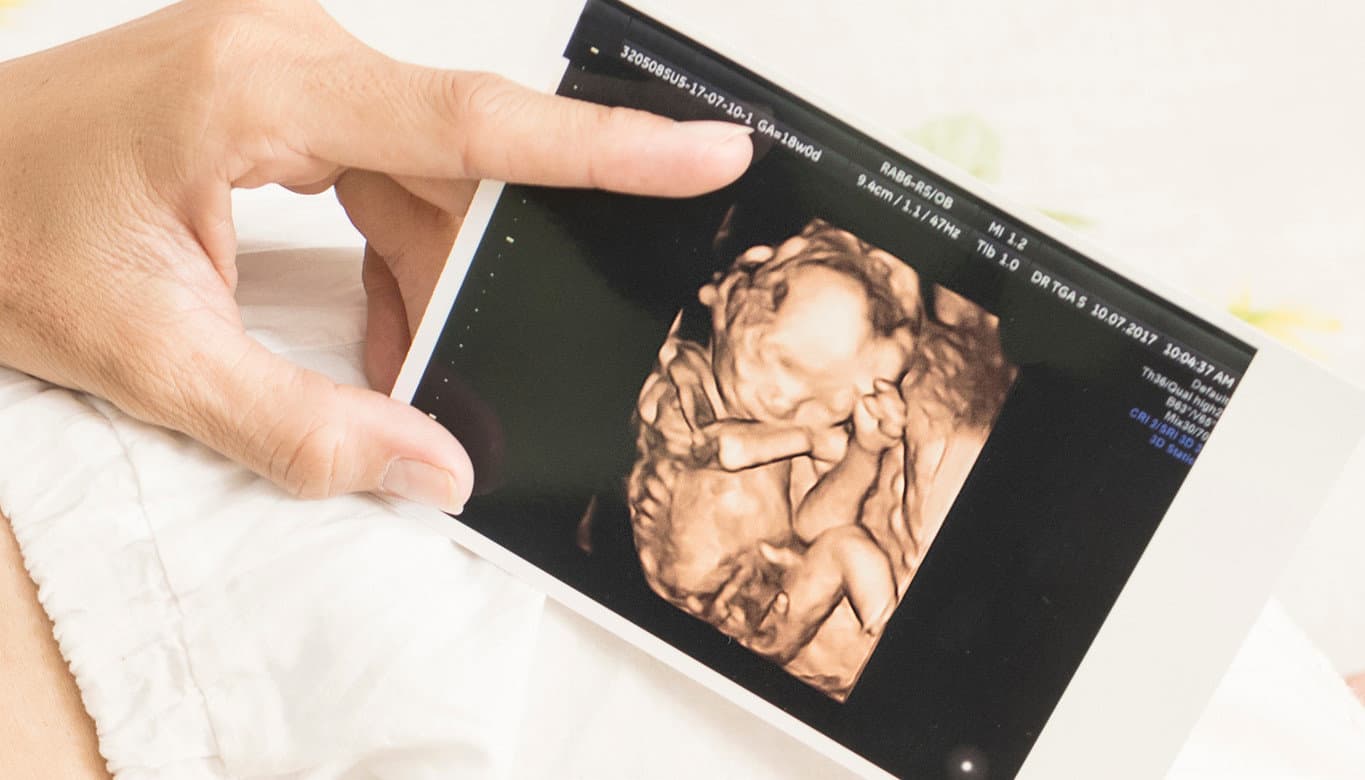

Ultrassonografia Obstétrica 3D | 4D | 5D Essa ultrassonografia oferece uma experiência mais imersiva e detalhada da gestação.

🔹 Diferenças:

3D: Imagem estática do bebê em alta definição.

✅ 4D: Imagem em movimento, mostrando expressões e movimentos do feto.

✅ 5D: Tecnologia avançada que proporciona imagens mais realistas e com melhor definição.

Além de proporcionar um vínculo emocional incrível, esse exame permite observar com mais detalhes a anatomia do bebê.